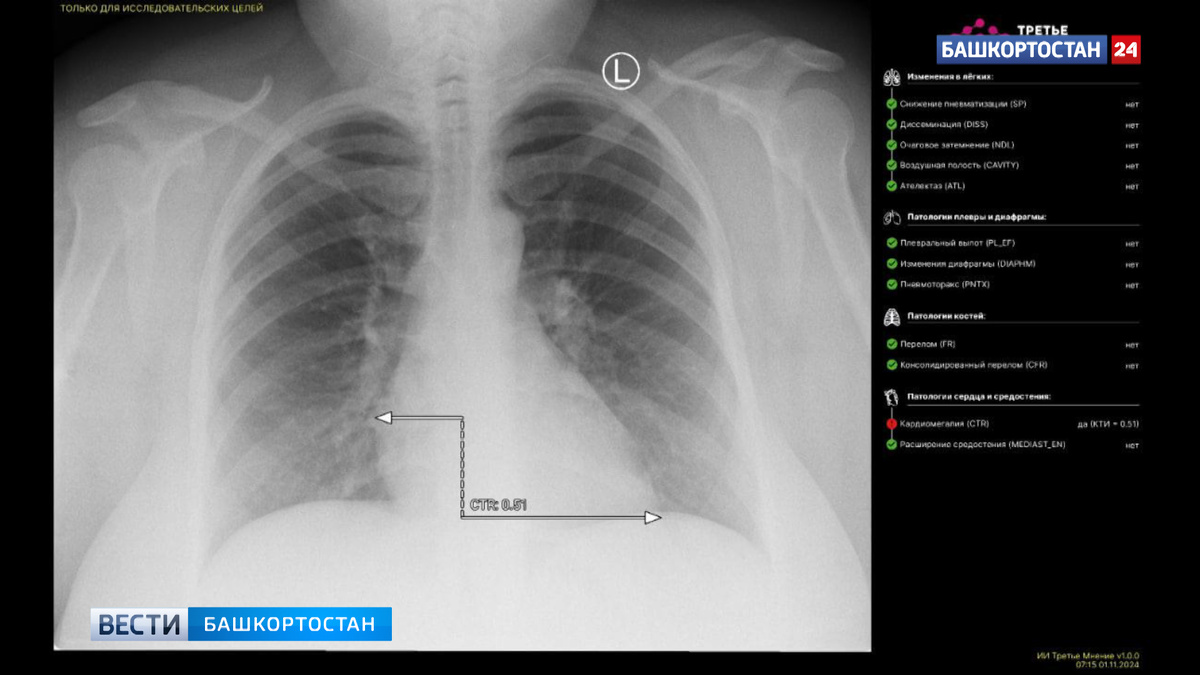

В Башкирии искусственный интеллект впервые расшифровал рентгеновский снимок пациента

В Уфе специалисты из городской больницы №21 отправили рентген органов грудной клетки пациента на специальную платформу «МосМедИИ». Через минуту они получили заключение от искусственного интеллекта.

"ИИ провел интерпретацию полученного медицинского изображения, разметил зоны патологических очагов и выдал протокол исследования. Это большой прорыв в области цифровизации здравоохранения. ИИ поможет оперативнее читать КТ, МРТ, рентгенснимки, флюорографию, ангиографию – все то, что сохраняется в «картинке». Стоит отметить, что последнее слово все же будет оставаться за врачом. До конца года планируется расширить как количество медицинских организаций, так и количество ИИ-сервисов, используемых республикой на «МосМедИИ». Все работы проводятся в рамках национального проекта «Здравоохранение», — поделился и.о. министра здравоохранения РБ.